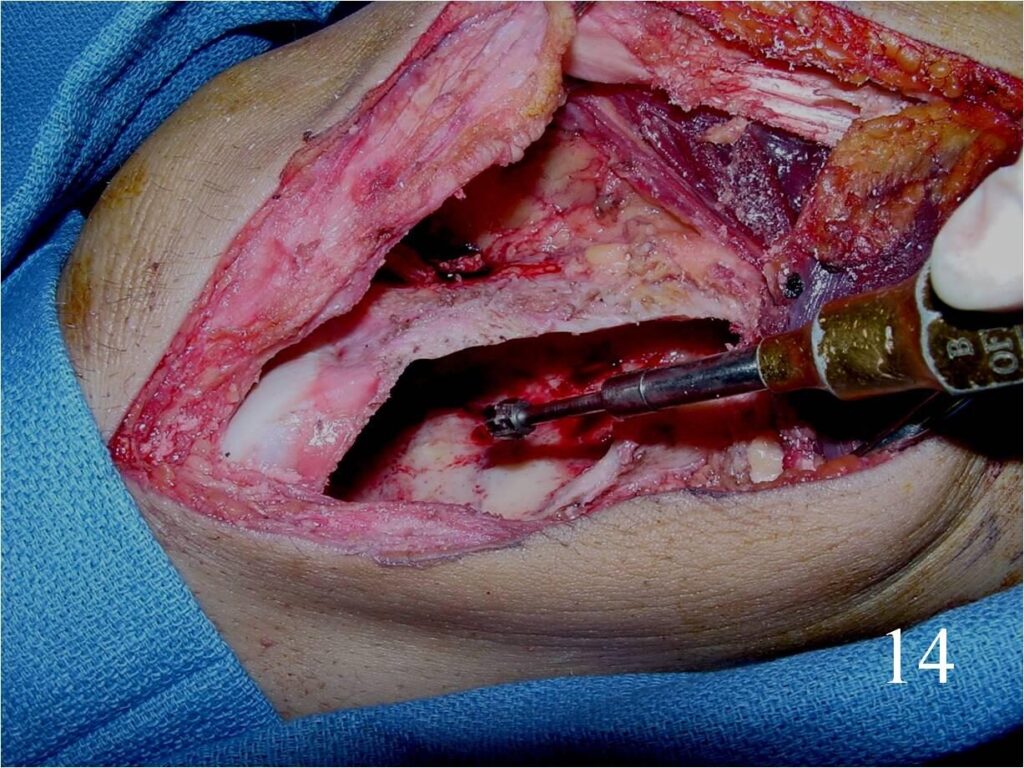

o Curettage, cement and possible internal fixation with hardware (Fig. 13, 14, 16)

Fig. 13 Intralesional curettage of the giant cell lesion and (Fig. 14) shaving the wall of the tumor cavity with high speed burr.